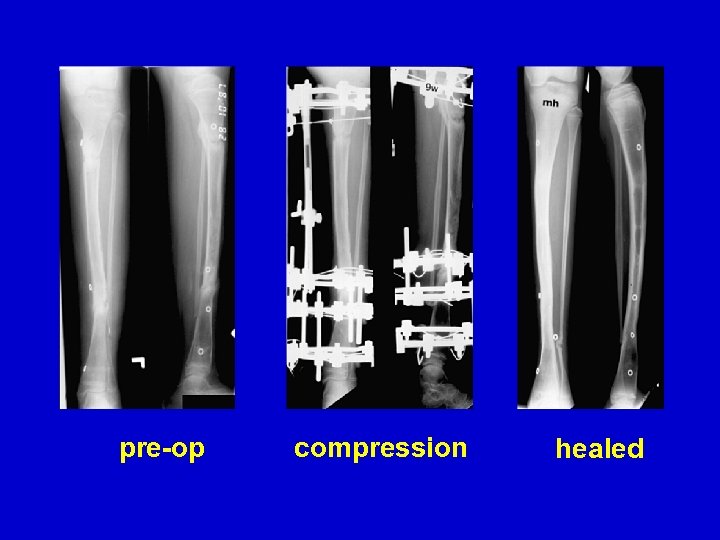

pre-op compression healed